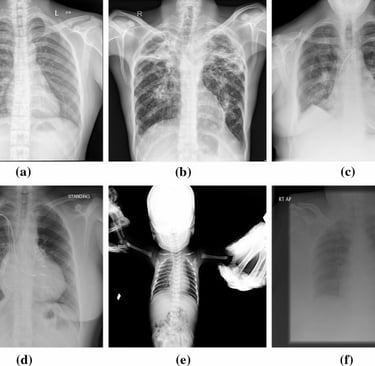

a. Start by Examining the Quality of the Image

Before diving into specifics, you need to evaluate the quality of the X-ray image. An unclear or poorly exposed X-ray can make it difficult to see the details necessary for accurate interpretation. Check for:

Proper exposure: Are all areas of interest clear and visible?

Good positioning: Is the patient’s body positioned correctly for the X-ray?

No motion blur: Is the image sharp, or does it look fuzzy due to patient movement?

d. Evaluate the Lungs and Heart (in Chest X-Rays)

A chest X-ray typically includes the lungs and heart. Here’s what to look for:

Lungs: Check the lungs for any abnormal spots, shadows, or consolidations (which might indicate infection like pneumonia or other lung conditions).

Heart: Ensure that the heart’s size and shape appear normal. Enlargement or abnormalities could indicate conditions such as heart failure or pericardial disease.

e. Consider the Positioning and Symmetry

Always keep in mind the positioning of the X-ray. Is the body aligned properly? In a PA (posteroanterior) chest X-ray, for instance, you would want the patient’s chest to be in an upright position to avoid distortion. Compare both sides of the body, especially if it’s a full-body X-ray, to identify any asymmetry or abnormalities.